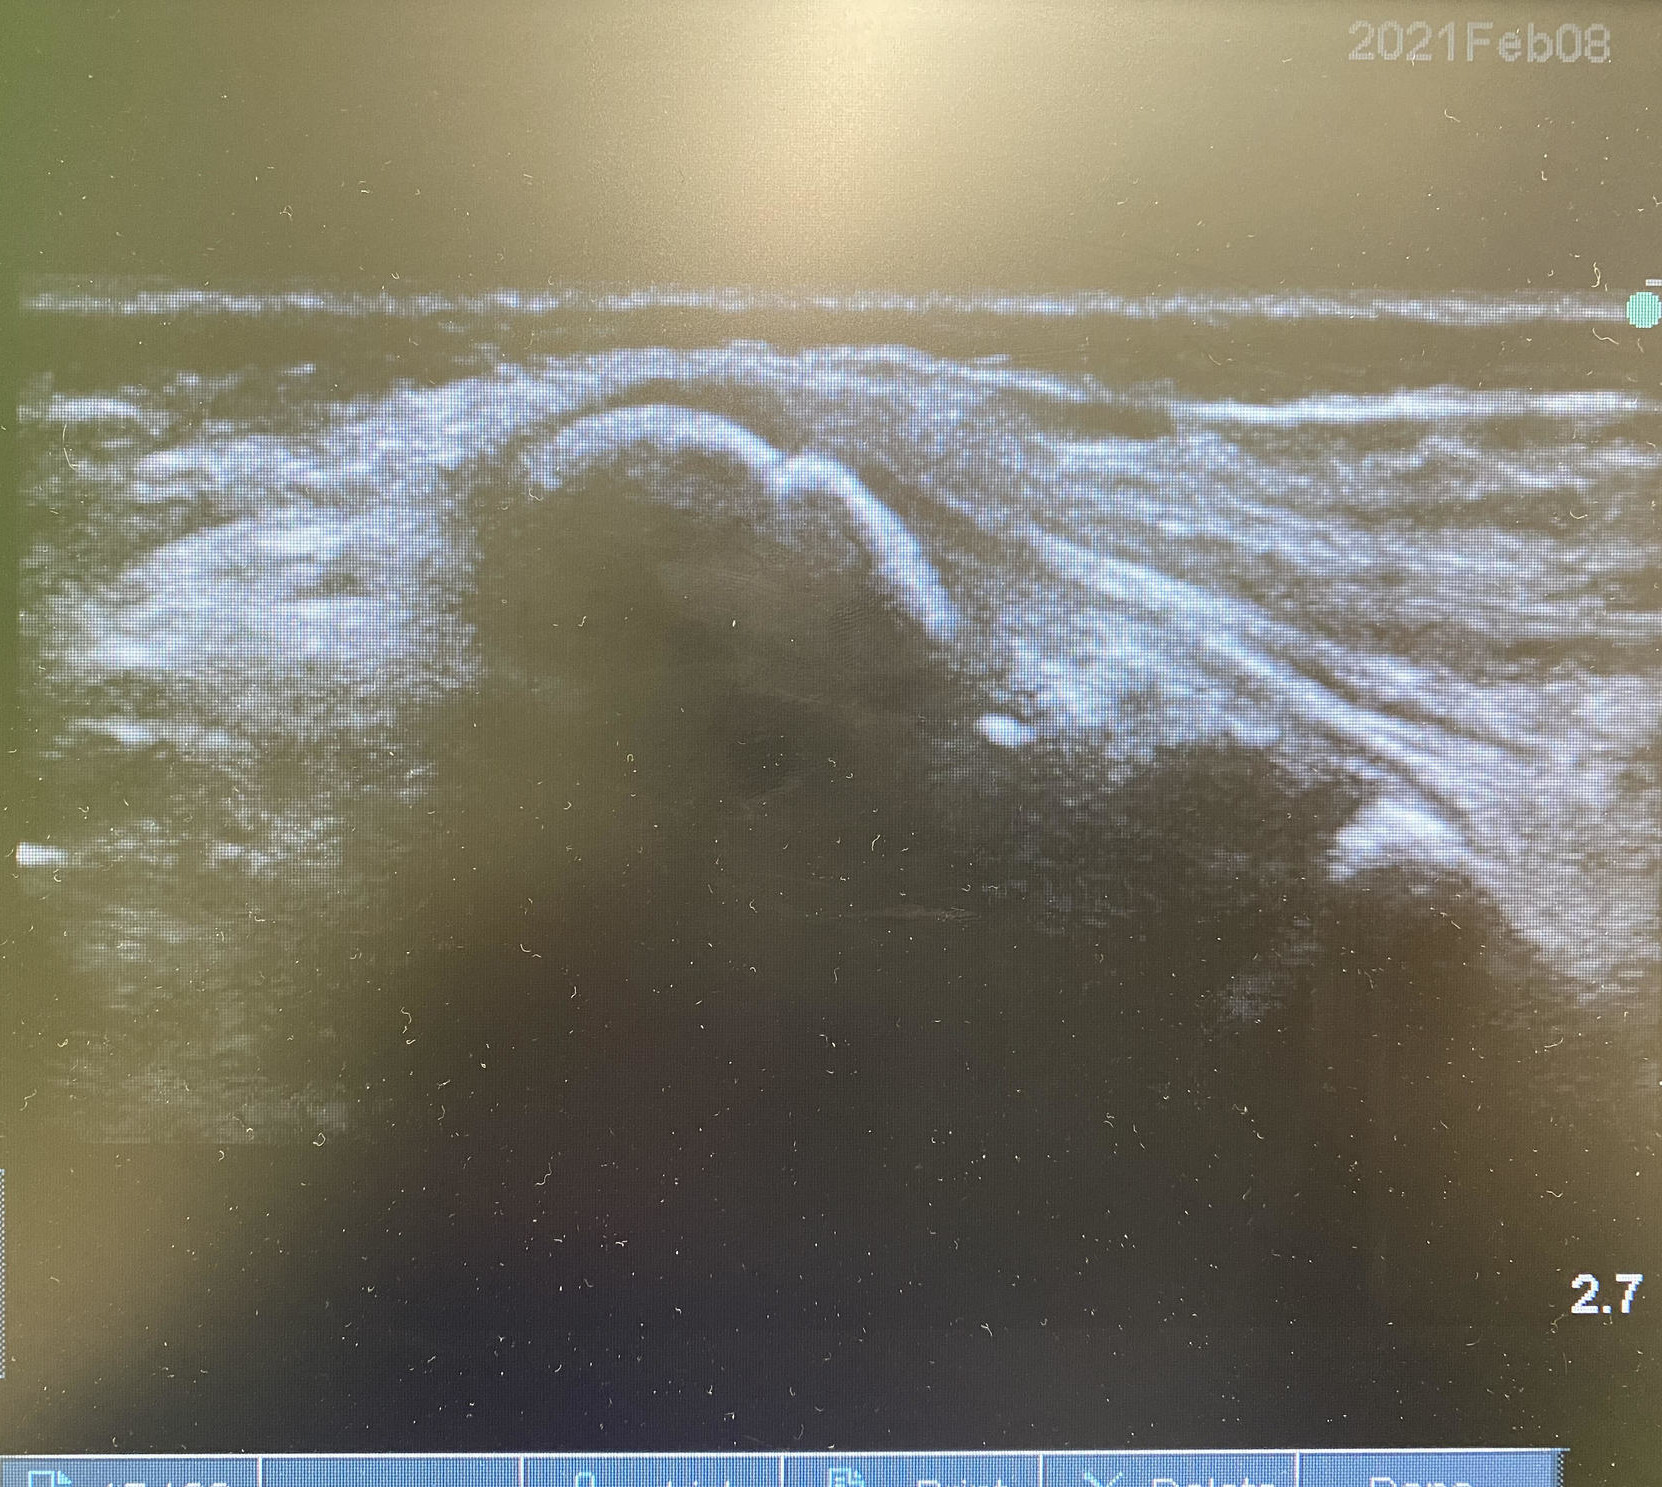

その為にも、エコーを用いたチェック!!!